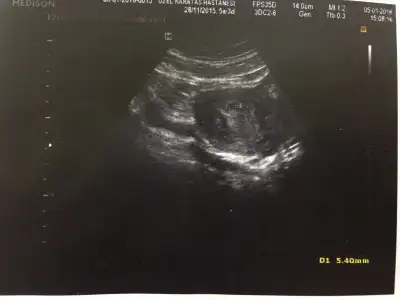

6+3 hafta kese boş

image.webp